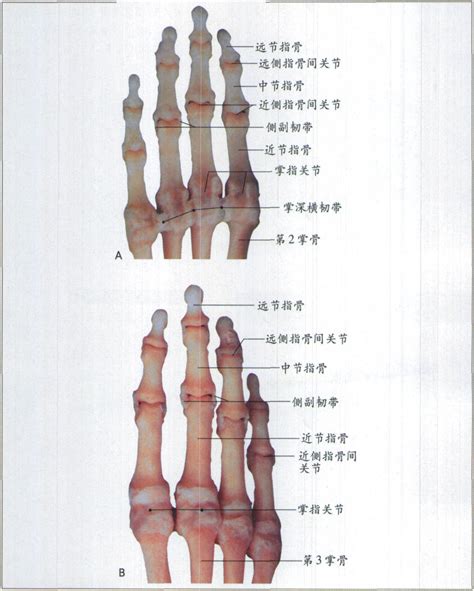

除了上述的生理和心理意义外,“示指”和“环指”在医学诊断和治疗中也发挥着重要作用。医生们常常通过观察手指的形态、色泽和触感等来判断患者的健康状况。例如,手指的肿胀、疼痛或麻木等症状可能是多种疾病的征兆,如关节炎、神经损伤或血液循环障碍等。此时,“示指”和“环指”作为手指的重要组成部分,它们的异常变化往往能够为医生提供重要的诊断线索。

此外,在中医理论中,手指与人体的脏腑经络有着密切的联系。通过按摩、针灸或刮痧等手法刺激手指上的特定穴位,可以调节人体的气血循环和脏腑功能,从而达到治疗疾病和保健养生的目的。在这一过程中,“示指”和“环指”同样扮演着重要的角色。它们上的特定穴位对应着人体的不同脏腑和经络,通过刺激这些穴位可以调理相应的脏腑功能,改善人体的健康状况。